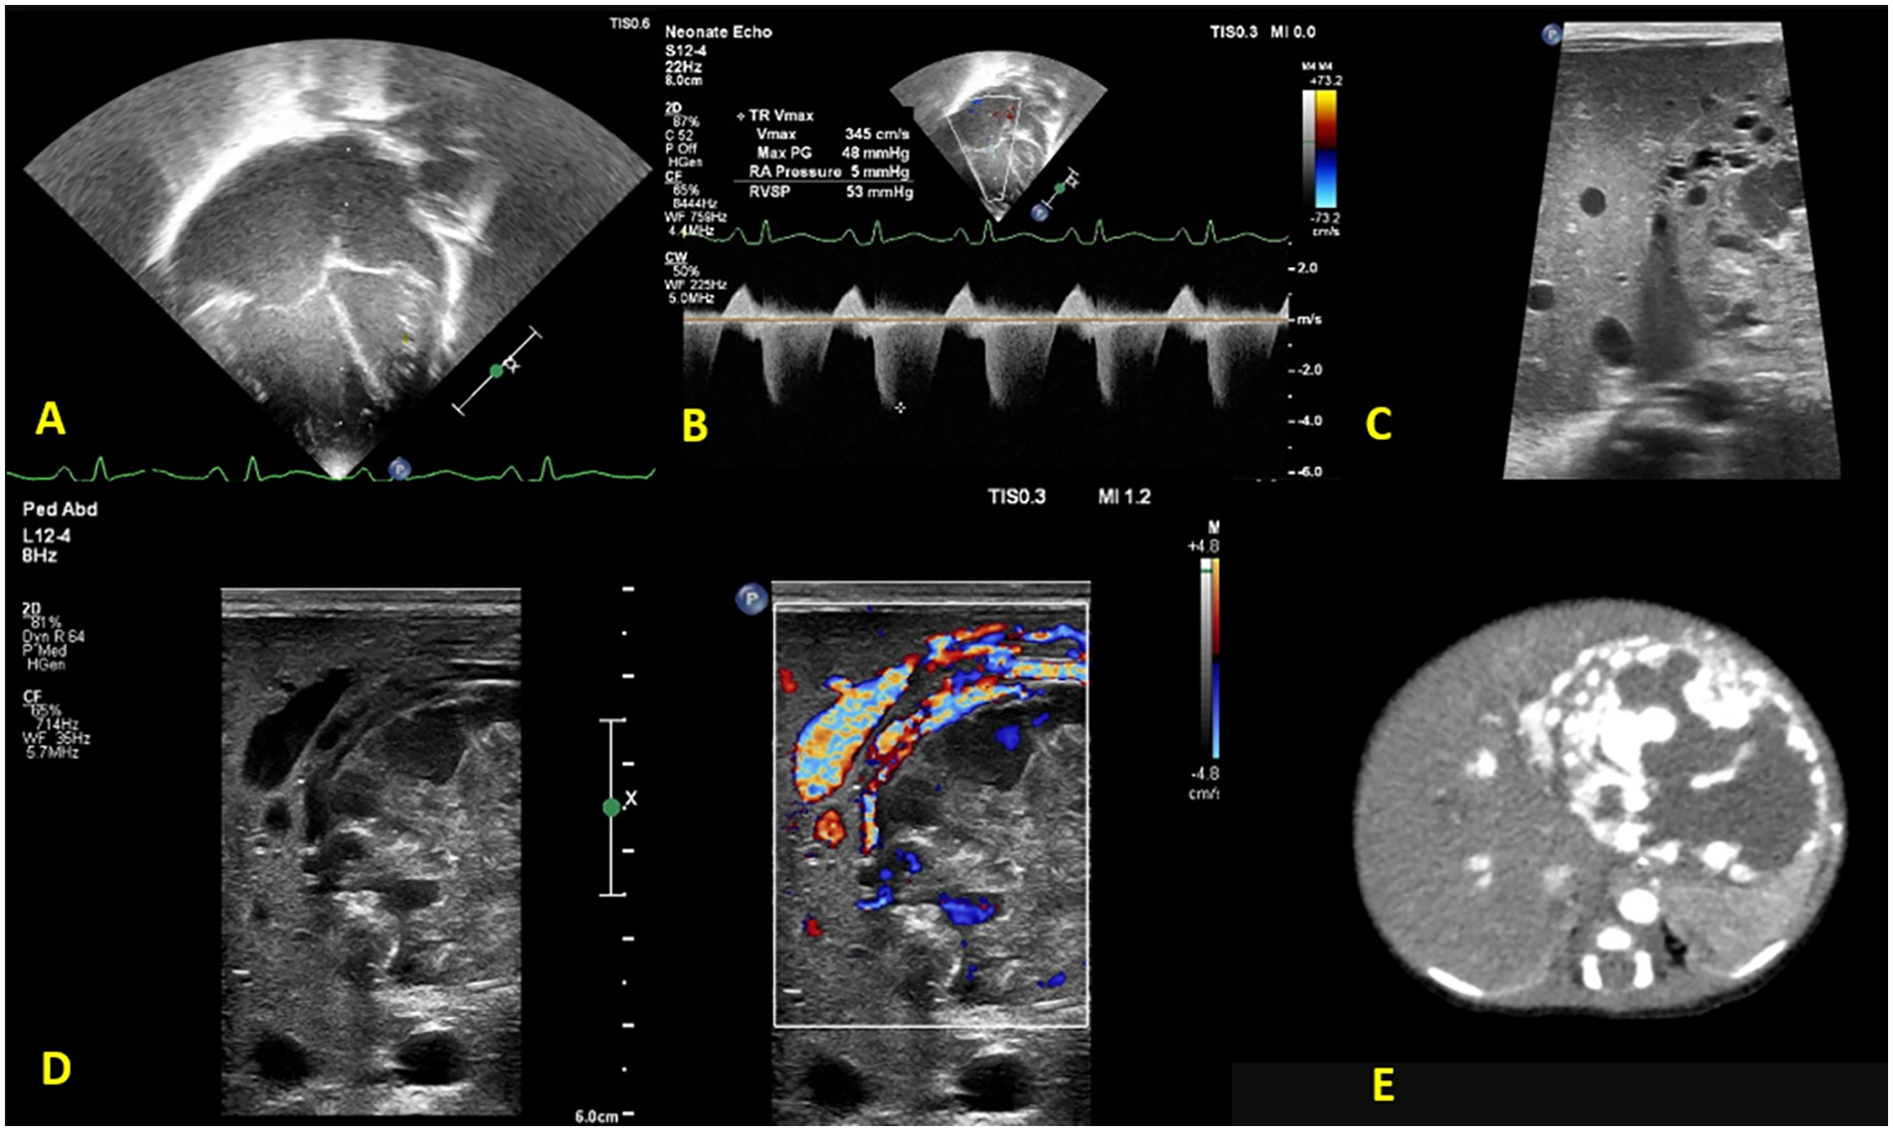

After initial stabilization, a bedside FnECHO was performed, which revealed a dilated right atrium and right ventricle, a high right ventricular output and normal left ventricular output, normal cardiac systolic functions, features of pulmonary hypertension (PH) [pulmonary arterial systolic pressure (PASP) by tricuspid regurgitation (TR) jet 50–55 mmHg] (Figures 1A,B), a D-shaped left ventricle, and a right to left shunting across the patent foramen ovale (PFO). The subcostal echocardiographic views showed a significantly dilated inferior vena cava (IVC) and left hepatic artery. A further interrogation of the liver revealed a non-homogeneous mass measuring approximately 5 × 5 cm in the left lobe of the liver, with excessive vascularity on Doppler evaluation, suggestive of a liver hemangioma (Figures 1C,D). The ultrasound findings were confirmed by the radiologist, and a subsequent CT abdomen revealed a well-defined oval lesion measuring 6 × 5 × 4.8 cm in segments II and III of the left lobe of the liver, suggestive of high-flow hemangioma, confirming the diagnosis (Figure 1E).

Figure 1

Functional echocardiography shows (A) a dilated right atrium and right ventricle (B) tricuspid regurgitation with pulmonary arterial systolic pressure 50–55 mmHg. Liver POCUS reveals (C) a non-homogeneous mass, measuring 5 × 5 cm in the left lobe of the liver with (D) excessive vascularity on Doppler evaluation, suggestive of a liver hemangioma. (E) Confirmatory CT abdomen with contrast.